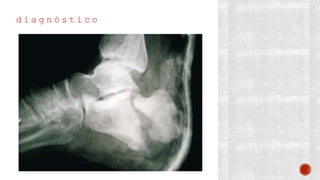

d i a g n ó s t i c o

¬ Clínico

¬ Radiográfico

- AP de pie

- Lateral de pie

- Axial de Harris

- De Broden

- Transversa

- TAC